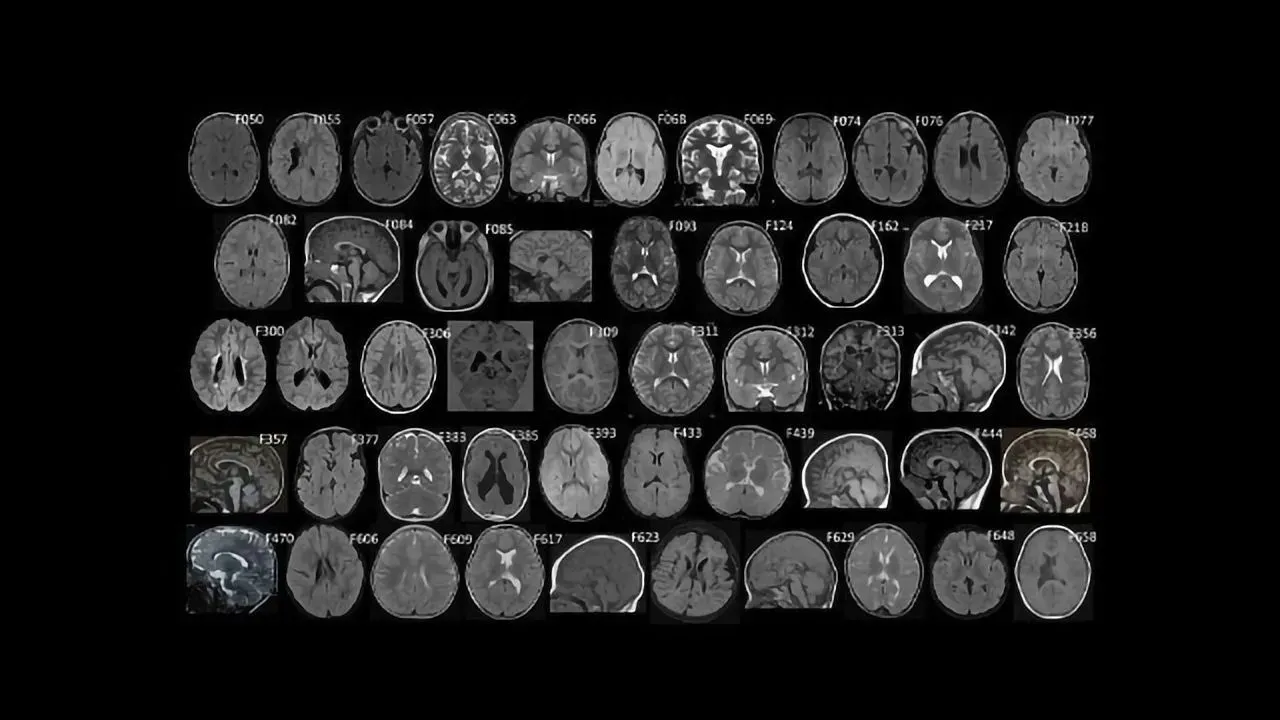

Could Genetics Play a Causal Role in Some Cases of Cerebral Palsy? – Technology Networks Friday, 2 October, 2020 Technology Networks

Brain Wiring Mutations Could Contribute to 14% of Cerebral Palsy Cases – Technology Networks Tuesday, 29 September, 2020 Technology Networks